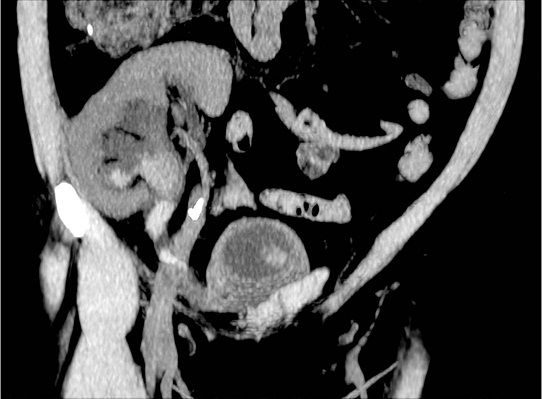

Figura 1. Pelvic computed tomography

Bladder lavage showed several clots. In the following 24 hours she progressed to hemorrhagic shock with respiratory dysfunction and need for invasive mechanical ventilation and progressive worsening of renal function, with serum creatinine of 4.55 mg/dL. Pelvic computed tomography (CT) revealed calyx and pelvis duplicity and ureter bifidity which merged into a single ureter and inserted into the right anterolateral wall of the bladder (Figure 2). The inferior ureter was enlarged due to an obstructive clot, close to the confluence between ureters, without dilatation of the superior one. She underwent a cystoscopy that revealed a large placenta of clots, and washing was done. Ventilatory weaning occurred without intercurrences and a double J ureteral catheterization was performed on the lower ureter with progressive improvement of renal function and resolution of hematuria. She was discharged on the seventh day of re-hospitalization.

Figura 2. Allograft Doppler Ultrasonography